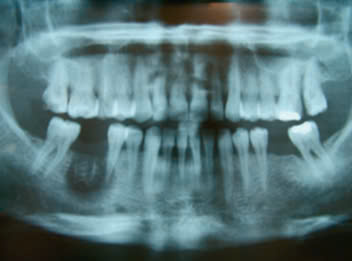

Hình 1: Hoại tử xương hàm ở vị trí răng 46 sau điều trị nội nha có sử dụng Arsenic5